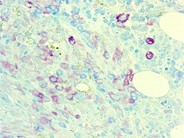

CD117 immunostain highlight the mast cell component in the infiltrate.